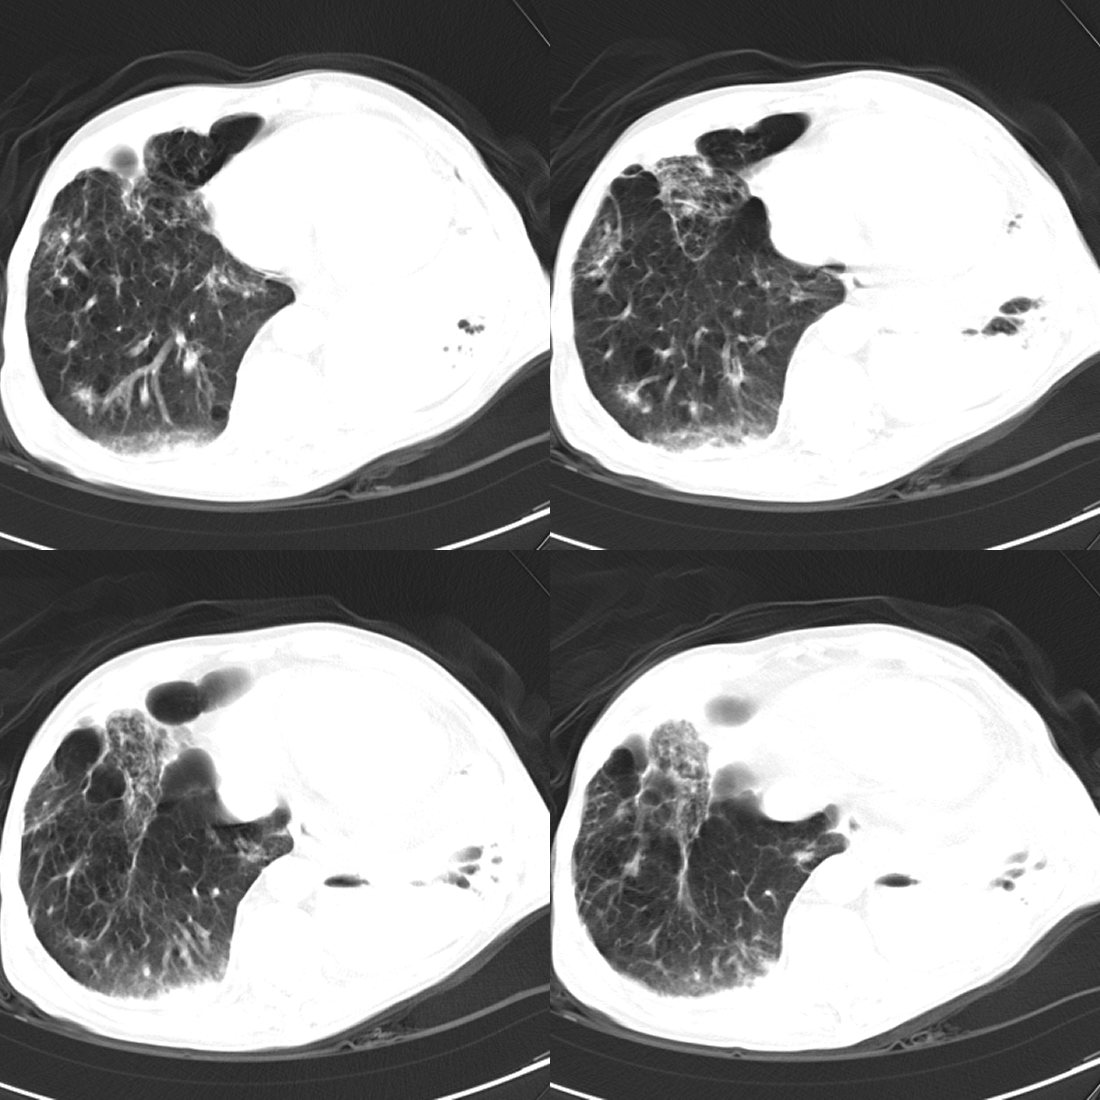

以下是引用liuyue在2008-11-30 6:01:00的发言:[br]双肺继发性肺结核;左侧包裹性积液;建议增强化或支气管镜检查除外左肺占位性病变.

以下是引用吴承学在2008-11-30 8:02:00的发言:[br]双肺继发性肺结核;左侧包裹性积液;建议增强化或支气管镜检查除外左肺占位性病变.[br]